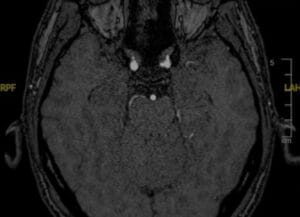

Cierre de fístulas de líquido cefalorraquídeo nasosinusales

Presentamos dos casos de cierre de fístulas de líquido cefalorraquídeo nasosinusales, abordados por el Dr. Alfonso Santamaría.